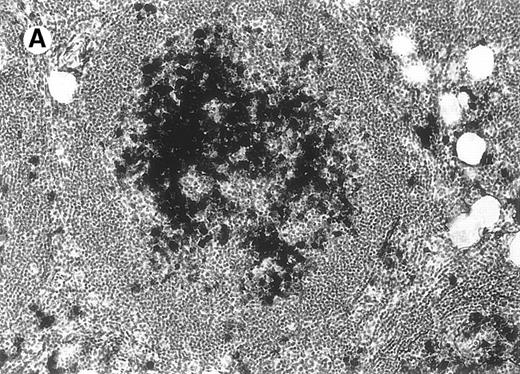

Cytomorphology.

Centroblasts and centrocytes evident within a follicle (patient 3).

All cases of follicular lymphoma were classified as grade 2 according to the REAL classification. Histology showed bottom-heavy lymphoid infiltrates with prominent follicular pattern (Figures3 and 4). A well-formed mantle zone around most follicles was present only in 2 patients. In the other specimens the mantle zone was either reduced (11 patients) or nearly absent (2 patients) (Figure5). A clear-cut marginal zone was never observed. Tingible body macrophages within follicles were present only in 1 patient and were absent in the other 14 patients. Cytomorphology of follicles in all patients showed variable proportions of centrocytes (cleaved follicle center cells) and centroblasts (Figure6). The interfollicular areas revealed the presence of small lymphocytes and histiocytes admixed with a few larger cells and occasionally other inflammatory cells such as eosinophils and plasma cells.